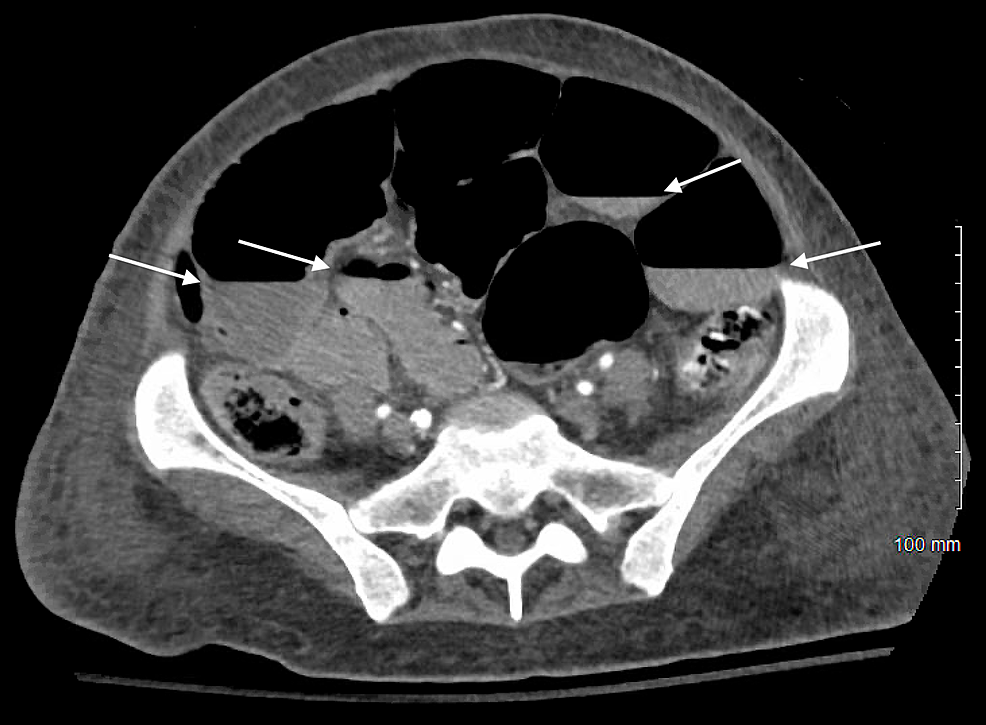

CT scan of the abdomen showing air fluid level in the small bowel Air Fluid Levels In Intestinal Obstruction Complete or high grade obstruction means that no fluid or gas can get beyond the obstruction. Incomplete, low grade or partial obstruction. The pathologic effects of acute intestinal obstruction are fluid and electrolyte imbalances, and mechanical consequences of increased luminal pressure on intestinal perfusion. The main aims of imaging in cases of suspected bowel obstruction are: Complete or high grade. Air Fluid Levels In Intestinal Obstruction.